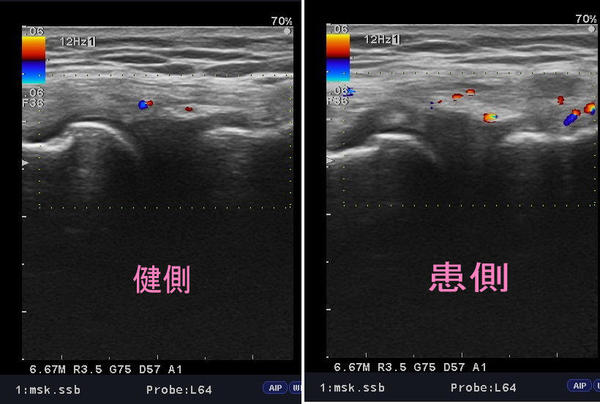

御来院後、超音波検査をしたところ写真左側健側の外側側副靱帯は、

靱帯部の繊維もしっかりと確認できます。

また、画像の中央部に青と赤の点がありますが、これは血流を表しています。

これに対し、患側の外側側副靱帯は、靱帯部の繊維も内出血した血液や炎症を抑えるために

出てきた水分によって不鮮明な画像になっています。

(※血液や水分は黒く映り、骨や靱帯など個体のものは白く映るため、血液や水分の多い所は黒く不鮮明になる。)

また、血流を見てみると、患側のほうが赤と青の点が多く診られます

これは、損傷した靱帯を修復しようと血行が豊富で、血流からも靱帯部が損傷していることがわかります。